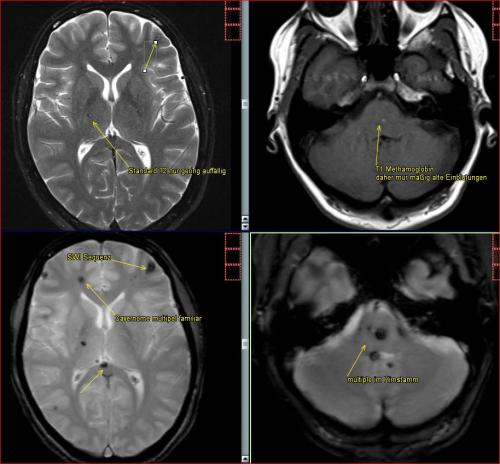

Aneurysma re. 7 mm Darstellung in einer DSA (digitalen Subtraktionsangiographie) links nur ein 2 mm „Baby-Aneurysma“ Im MRT war zuvor das linke Aneurysma aufgefallen, die Auflösung einer DSA ist technisch im MRT nicht erzielbar, beide A. liegen in der ACM Bifurkation jeweils, das re. Aneurysma wurde erfolgreich operiert, das linke Aneurysma wird kontrolliert.